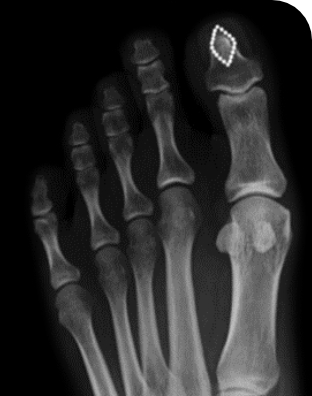

소건막류는 새끼발가락 아래쪽 외측이 튀어나와서 신발과 부딪혀서 통증이 발생하는 질환입니다. 이 질환은 새끼발가락뼈가 아닌 5번째 중족골의 머리 부위가 외측으로 돌출되는 것이 원인이며, 통증이 계속된다면 튀어나온 뼈를 절제하거나 관절 윗부분에서 새끼발가락을 내측으로 밀어 넣는 수술을 시행합니다.

소건막류 역시 무지외반증과 마찬가지로 뼈가 변형됐기 때문에 정형외과적 수술이 유일한 치료방법입니다. 작은 절개만으로 교정이 가능하고 수술시간 또한 15~20분 정도로 아주 짧습니다. 또한 소건막류의 근본적인 원인을 개선할 수 있고 수술 후엔 발 폭이 줄어드는 효과도 기대할 수 있습니다.

수술 전, 후 사례 1

수술 전

수술 후